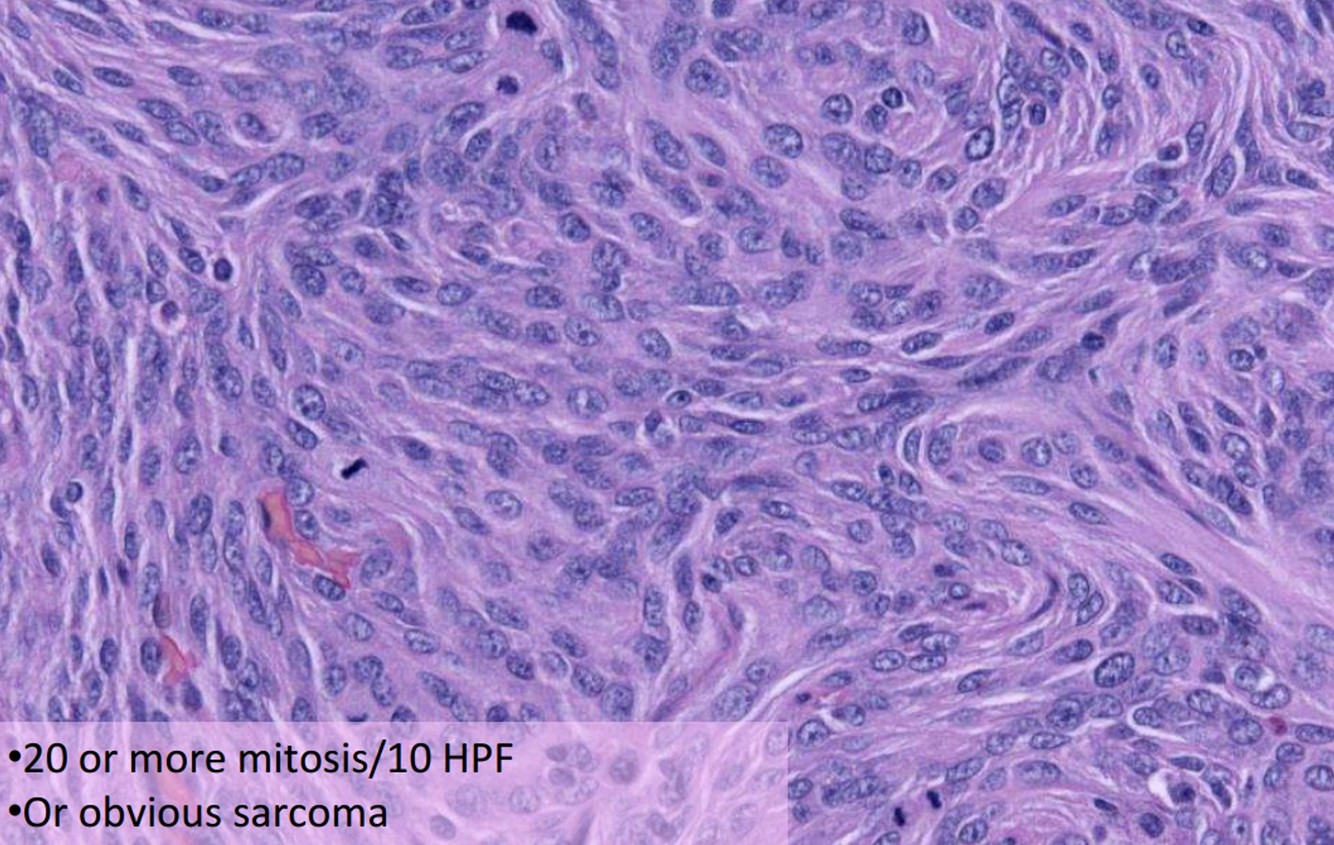

Anaplastic Meningioma